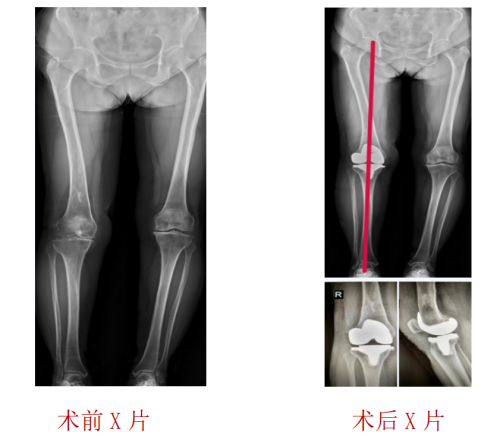

运动医疗、关节骨病科主任、主任医师丑克了解到,对平时走路散步时的疼痛程度张阿姨还能忍受,但是上下楼梯或者爬山、下蹲时就会明显感觉疼痛加重,只有休息后症状才能稍减轻,以前年轻时还有过右股骨下段化脓性骨髓炎病史,导致股骨畸形。医生经过仔细体格检查并结合影像学检查结果,诊断张阿姨患上的是“右膝关节退行性病变”。因张阿姨既往有过化脓性骨髓炎,为提高治疗效果,运动医疗、关节骨病科医护团队为张阿姨制定了个性化的手术治疗护理方案,术中使用IKPAS全膝关节导航定位技术,不开髓,减少手术创伤,精准定位截骨为张阿姨完成全膝关节置换手术。

术后医护团队对张阿姨全程进行ERAS理念管理,术后第二天她就能下床行走了,并且伤口愈合良好,也不感觉痛,术后第3天膝关节活动度可以达到90°。一周后,张阿姨出院了,她拉着丑主任手送上了锦旗:“我终于不用再受膝关节痛的折磨了,真的非常感谢您们!”

“IKPAS全膝关节手术定位系统利用传感器技术,不依赖术前患者的影像数据,通过陀螺仪及加速度计配合特定的算法,在术中实时测量股骨远端与胫骨平台的截骨角度,计算获得个性化的角度数据,以辅助医生更加精准地完成膝关节置换手术中下肢力线测量和截骨定位,被称之为智慧型膝关节置换手术。”丑克主任介绍,该定位系统可用于初次和复杂膝关节置换手术,与传统的关节置换手术相比,智慧型膝关节置换术将误差控制在1°以内,具有不需打开髓腔、减少术中术后出血、提高截骨精准度、缩短手术时间、有效降低并发症发生等优势,而且在不改变医生手术习惯和操作流程的基础上,达到了轻、快、准的微创治疗要求。

丑克主任表示,因患者有过化脓性骨髓炎导致股骨侧畸形,不适合常规的开髓定位,使用IKPAS全膝关节手术定位系统可实现不开髓手术,且有效减少术中术后出血,实现手术微创化、精细化,避免骨髓炎的再次发生。智能化手术的实施不但提升了关节骨科医疗技术水平和手术疗效,也为骨关节病患者实现更标准、更规范、更安全的治疗提供了多种选择。